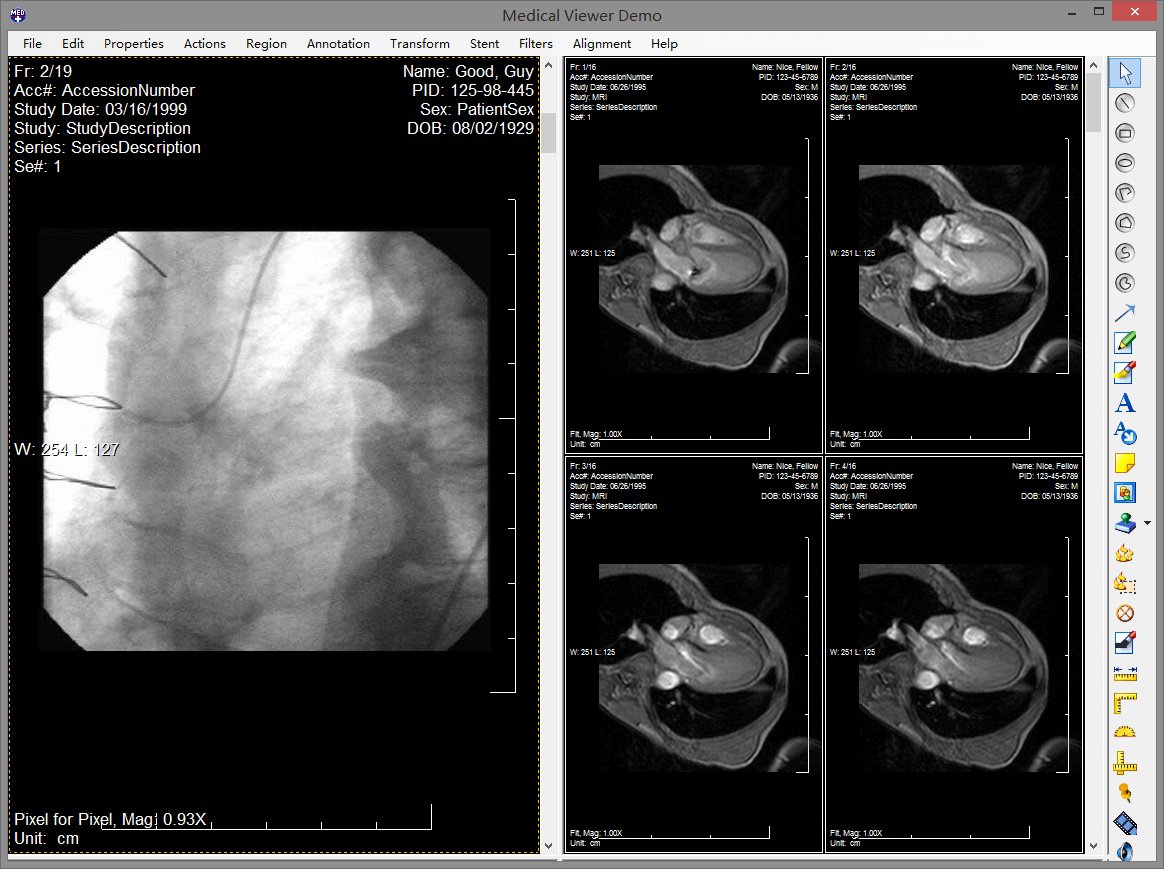

leadtools pacs能够使开发人员非常容易的开发一整套完整的pacs解决方案,组建企业级pacs服务器和客户端,实现dicom通信、查询、存储dicom影像数据。leadtools拥有成熟的pacs框架,您只需要修改logo就可以轻松构建一整套pacs系统。它包含了全套的权限、服务、存储、客户端、html5 web 端,而这一切都是基于多年大型医院需求的总结体现,并且已经完整的在超过150家医院真正部署。